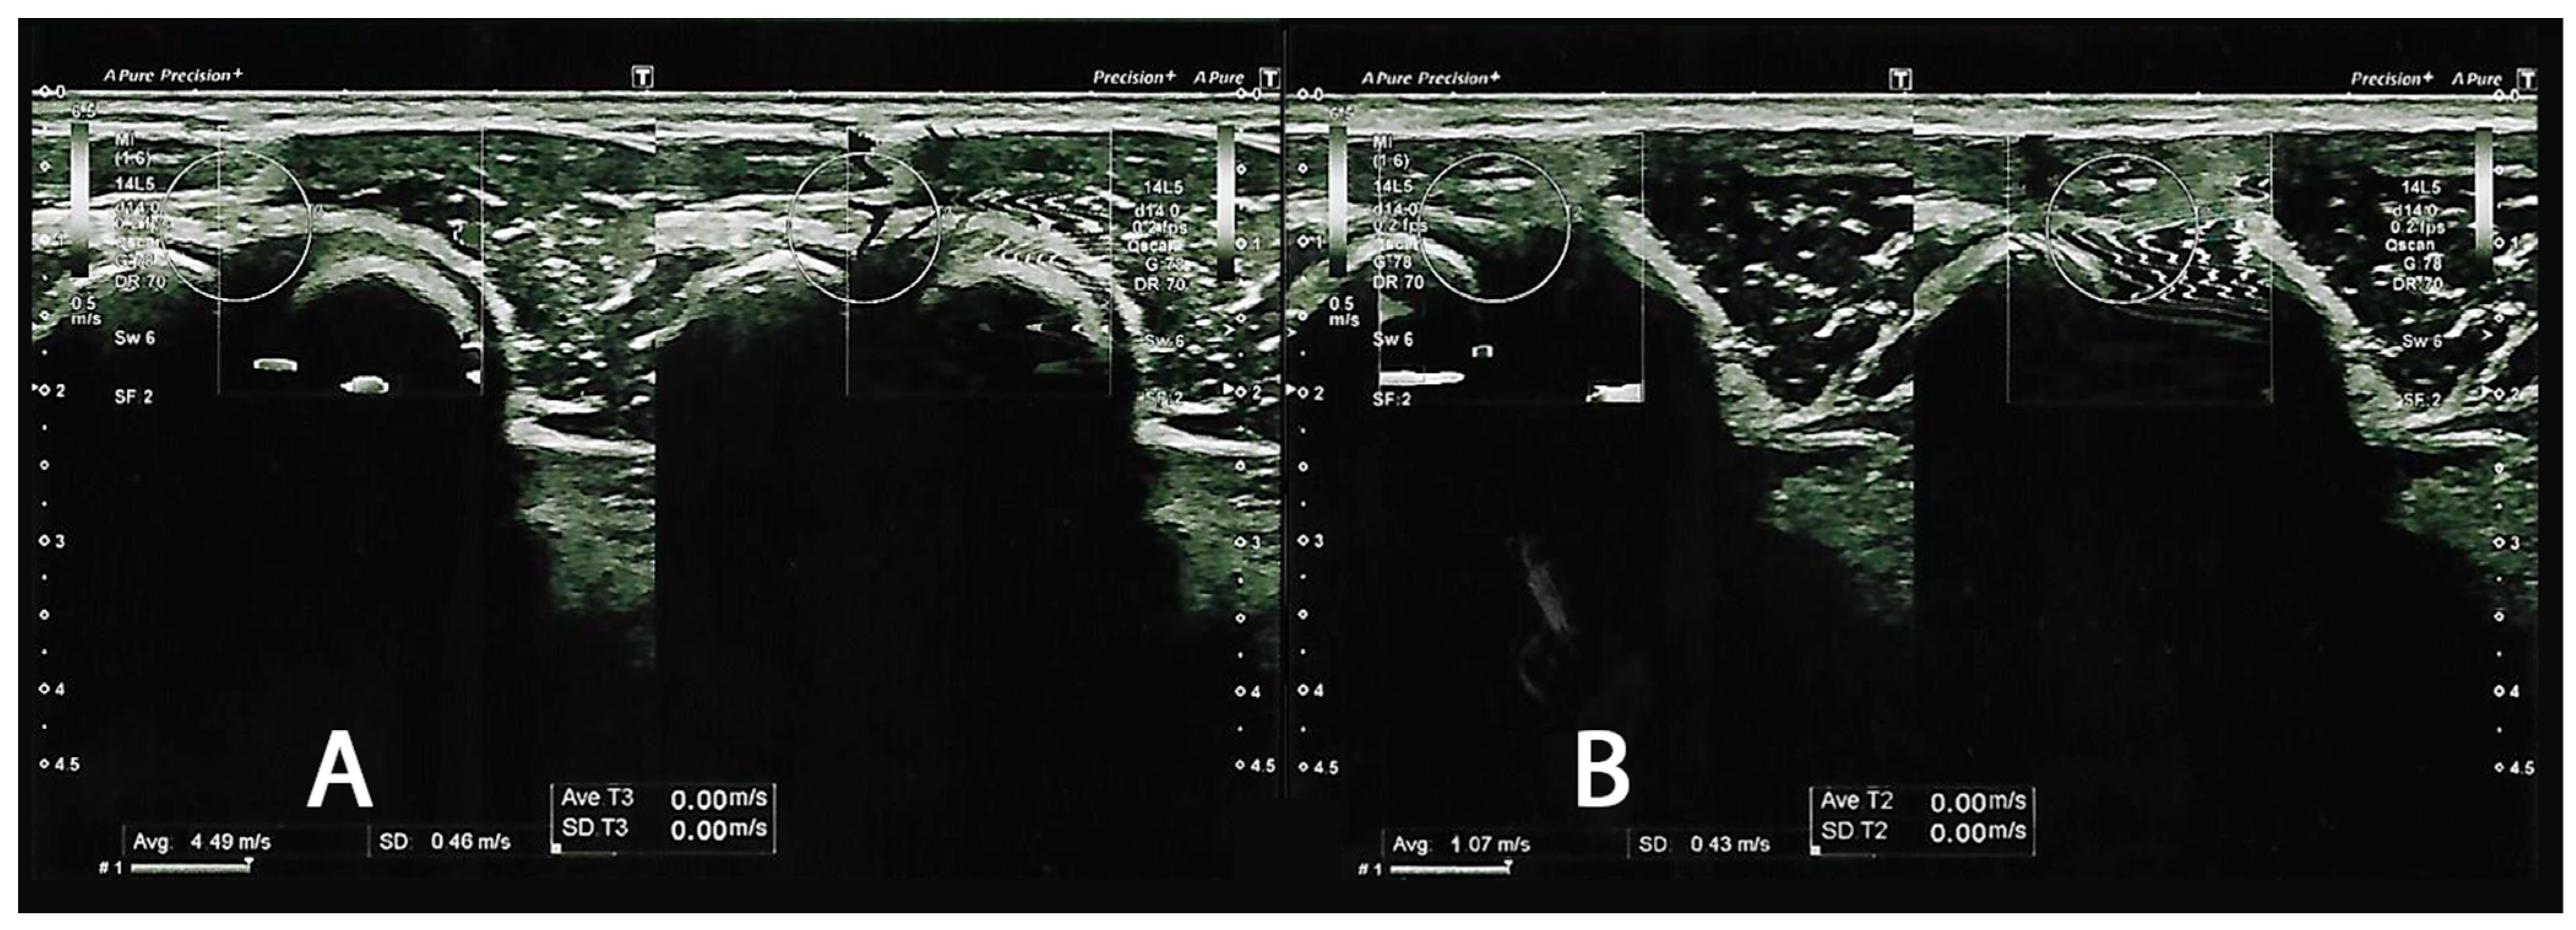

In total, sixteen subjects (13 males and three females) who met the study eligibility criteria were included and observed in the follow-up assessment. The mean age of the participants was 40.4 ± 5.53 years (min: 29, max: 51). Moreover, we reported a BMI of 26.8 ± 2.51 (min: 23.9 kg/m2, max: 33.1 kg/m2). We reported no dropouts from the study, nor did we report any adverse effects, even at the 4-week follow-up. As reported in Figure 2, we reported how we evaluated the elastograms for the healthy sides and the sides affected by LE, demonstrating the respective SWSs.

Shear wave velocity elastograms. (A) depicts a frame of the healthy lateral common extensor tendon (CNT), reporting a shear wave velocity of 4.49 m/s. (B) represents a picture of lateral epicondylitis (LE), reporting a shear wave velocity of 1.07 m/s.

During the baseline subject assessment, we reported that the LE side group had a noticeable severity of pain (NRS: 6.13 ± 0.96), compared to the healthy CNT side (NRS: 0.69 ± 0.79). In parallel, we reported a difference in SWS (CNT: 3.84 ± 0.51 versus LE: 1.69 ± 0.35), with results comparable to the study of Hong et al. [7]. At T1, all outcomes for the side affected by LE improved significantly, as reported in Table 1.